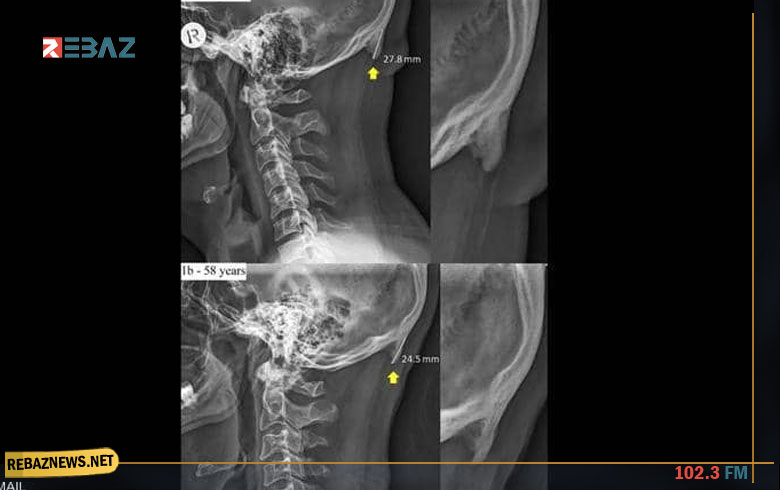

وبحسب ما نقلت صحيفة "ديلي ميل" البريطانية، فإن الشخص الذي يكثر من استخدام الهاتف الذكي، يظهر لديه ما يشبه شوكة عظمية في الجهة الخلفية من جمجمة الرأس، بسبب الانحناء والتركيز في شاشة الجهاز.

وتوضح الدراسة التي جرى إعدادها في جامعة "سان شان كوست" الأسترالية، أن جمجمة الإنسان أضحت تحدث هذه "الشوكة العظمية" بشكل متزايد.

وتبرز هذه الشوكة العظمية بشكل أسرع لدى الشباب الذين تتراوح أعمارهم بين 18 و30 سنة، واعتمدت الدراسة على عينة من ألف جمجمة.